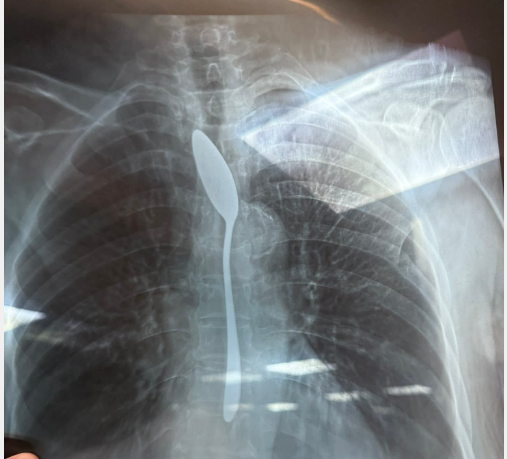

نجح فريق طبي بقسم الجراحة العامة في مستشفى شبين الكوم التعليمي بمحافظة المنوفية في إجراء عملية دقيقة لاستخراج ملعقة من بطن سيدة مسنة تبلغ من العمر 70 عامًا.

وقال الدكتور أحمد شهاب، طبيب الجراحة العامة بالمستشفى، إن المريضة وصلت إلى قسم الطوارئ بصحبة نجلتها التي أوضحت أن والدتها قامت بابتلاع ملعقة صغيرة بالخطأ، ما تسبب في شعورها بآلام شديدة.

وأضاف أنه تم إجراء أشعة فورية للمريضة، والتي أكدت وجود جسم معدني داخل المعدة، وعلى الفور تم تجهيز الحالة ودخولها غرفة العمليات، حيث تمكن الفريق الطبي من استخراج الملعقة خلال مدة قياسية تراوحت بين 5 و7 دقائق فقط.

وأكد الفريق الطبي أن المريضة بحالة مستقرة بعد العملية، وتم وضعها تحت الملاحظة الطبية للاطمئنان على سلامتها.